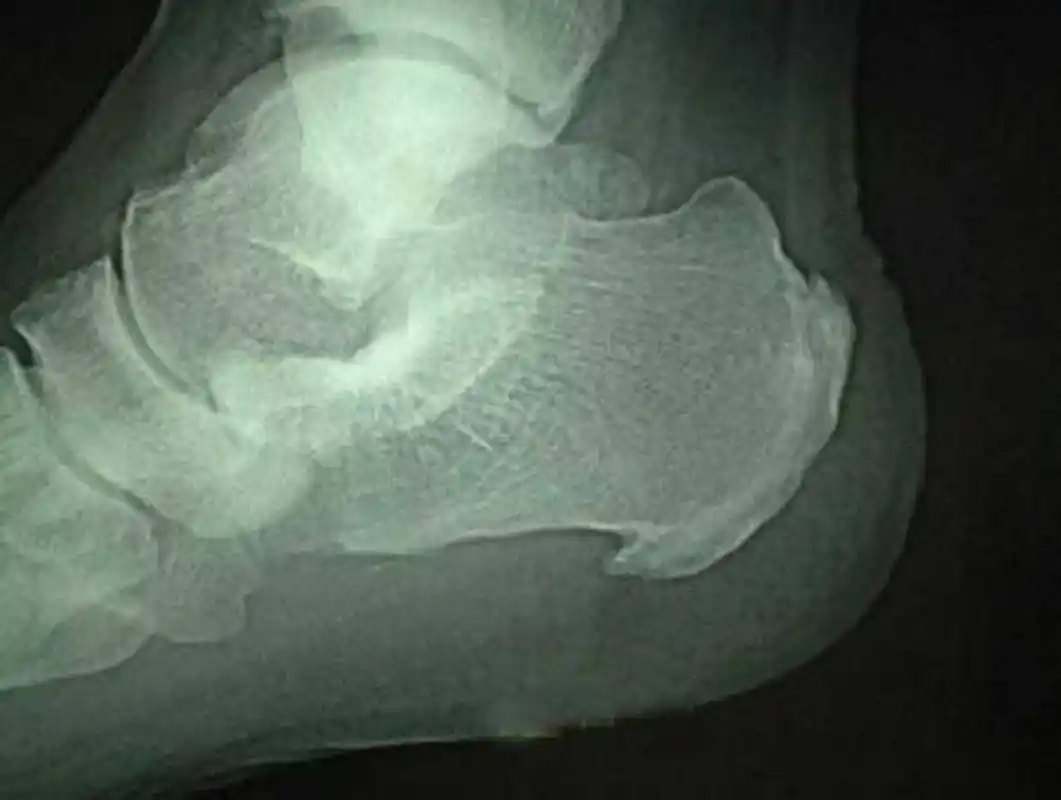

有关,当足跟关节出现磨损,破坏以后,人体自身会进行自我的修复,增生